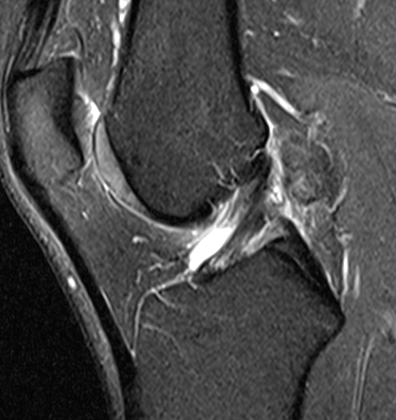

Diffuse

Diffuse PVNS with involvement of suprapatella pouch and posterior compartments, including posterior extra-articular